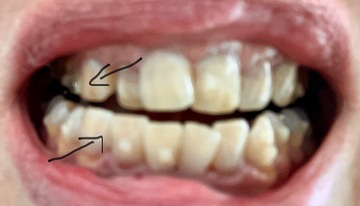

オーラルエステです今日は被せ物(補綴物)の種類を紹介

インレー

クラウン

ブリッジ